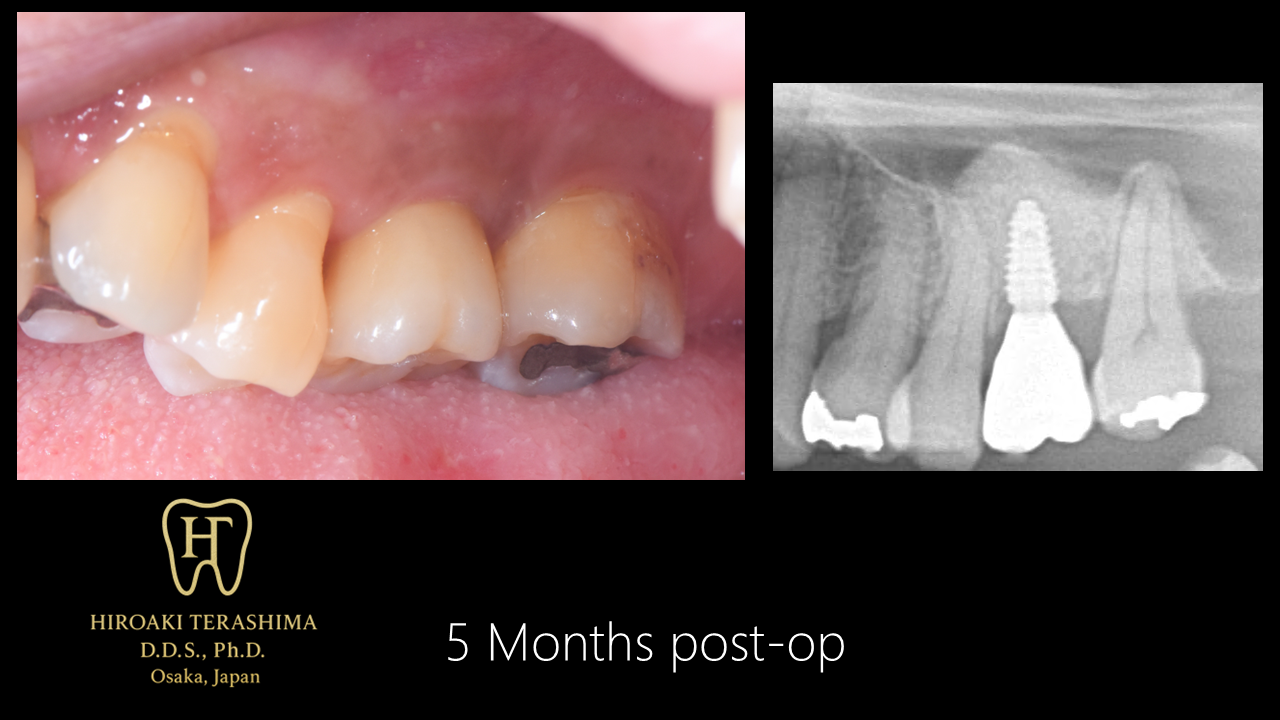

【経過】

X線でもインプラント周囲骨の成熟化が確認できました。